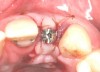

Fig 3. Osteotomy drilled into the ridge, occlusal view.

Figure 3

Fig 4. Implant inserted into the ridge, buccal view. There was a large labial concavity. The implant is seen on the buccal and terminates within the alveolar bone.

Figure 4